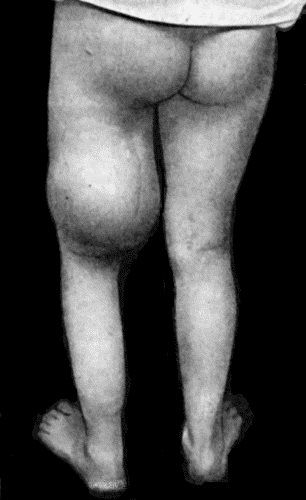

135.Cadaver, illustrating the alterations in the Lower Limbs resulting from Ostitis Deformans 475

136.Osteomyelitis Fibrosa affecting Femora 476